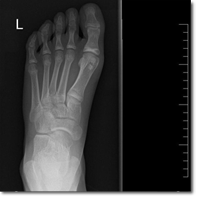

Niña de 12 años que acude a la consulta de Atención Primaria por chasquido en el tobillo de...

Ibarzabal Arregi M, Álvarez Zallo N, Duart Clemente J.

09 diciembre 2025